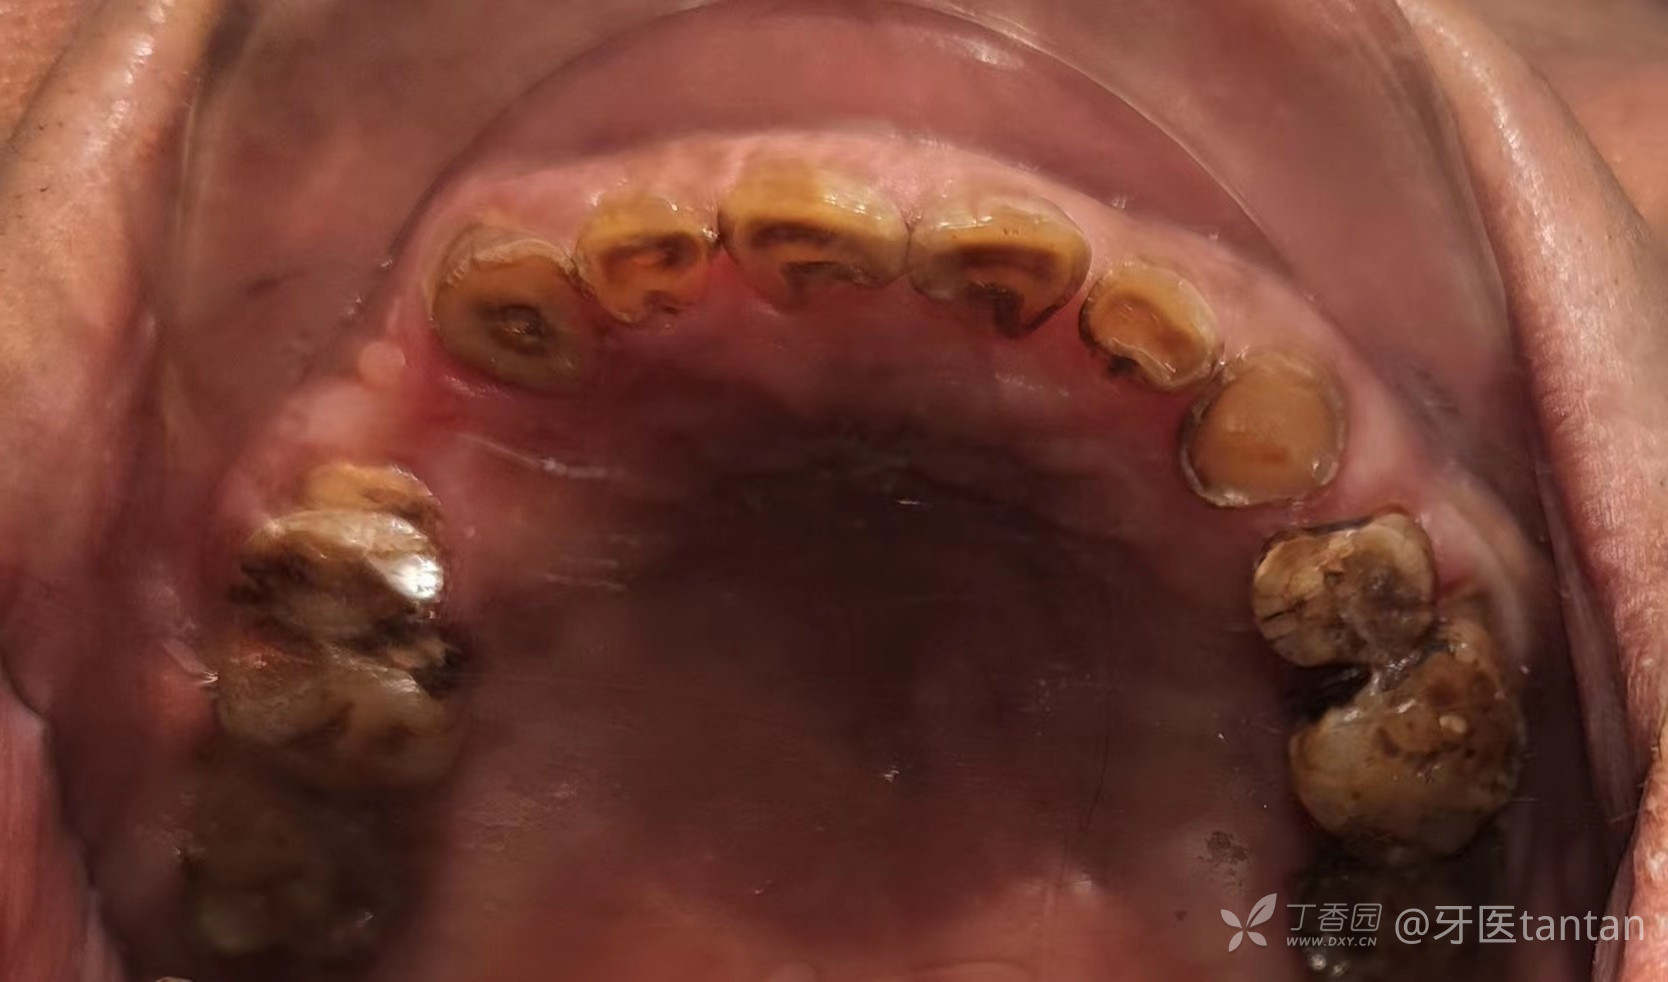

上颌牙列。